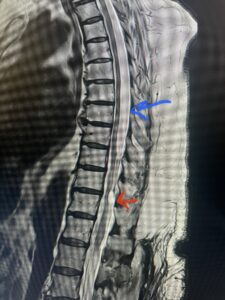

Fig. 1 Sagittal T2-weighted thoracic MRI demonstrating both T10-11 focal intradural arachnoid cyst (red arrow) and larger upper thoracic cyst that appears to extend from T4-T8 (blue arrow).

This 67-year-old female presents with progressive heaviness and numbness of the legs and difficulty ambulating. Her right leg was worse than her left. She had right greater than left hip flexor weakness. She was hyperreflexia in her lower extremities. An MRI (Fig. 1) demonstrated an intradural arachnoid cyst at T10-11 with severe spinal cord compression. She also appeared to have an arachnoid cyst above from T4-T8 with anterior displacement and compression of the spinal cord. Because of her severe myelopathy and the findings on MRI the patient underwent laminectomy for surgical decompression of cyst. Intraoperatively the focal arachnoid cyst at T10-11 appeared as a small bubble crushing the spinal cord anteriorly with scarring of the arachnoid with no CSF flow above or below.

The cyst was fenestrated and immediately CSF flow was reestablished. We performed a laminectomy at T6-7 for the upper cyst region which was observed to be more consistent with normal anatomy. We fenestrated the arachnoid. It was felt that the upper level was a secondary phenomenon as a result of CSF flow blockage. Post operatively she had an uneventful course with return of normal strength although she had some residual numbness.